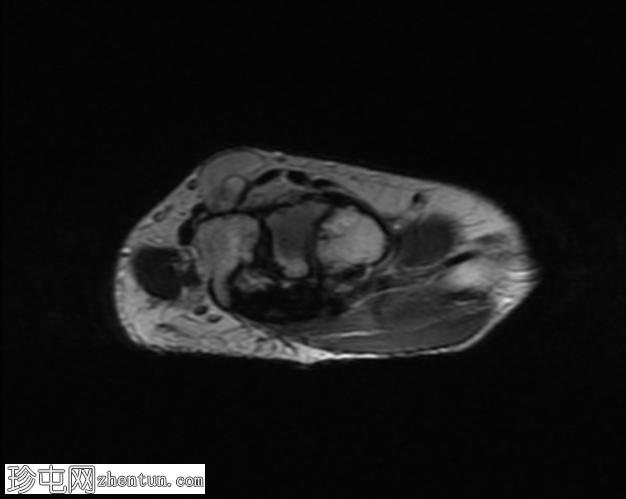

轴向

T2

无名指和中指明显增大。患者掌骨和指骨骨质增生肥大,并伴有周围皮下脂肪过度增生。

支配患指的正中神经掌侧支纤维脂肪瘤性错构瘤。它们在矢状面序列上呈现意大利面条状,在轴位图像上呈现绳索状。